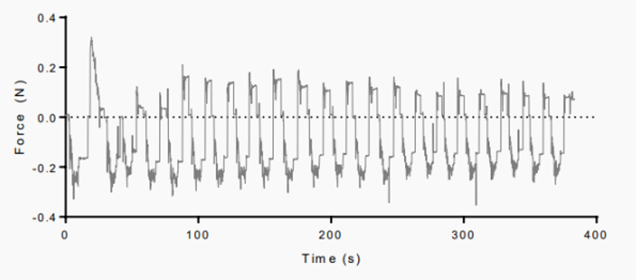

为了评估市售支架的机械性能,Opie等人在支架通过4个1.10 mm内径导管输送时施加力。支架头被连接到一根直径为0.3 mm的不锈钢棒上,固定在一个记录在10 Hz的力传感器上。将支架在室温下浸泡在生理盐水中,并使用微操作器以200 μm/sec的恒定速度从导管中展开或缩回。这个过程重复了至少200个循环。初始20个循环的张力试验结果如图7所示:前3个张力最高,之后最大力保持相对稳定。从最初的三次运行到最后的三次运行,力的平均减少了0.096±0.037 N。

图7 从1.10 mm内径导管中输送的薄膜支架的输送和收缩力痕迹